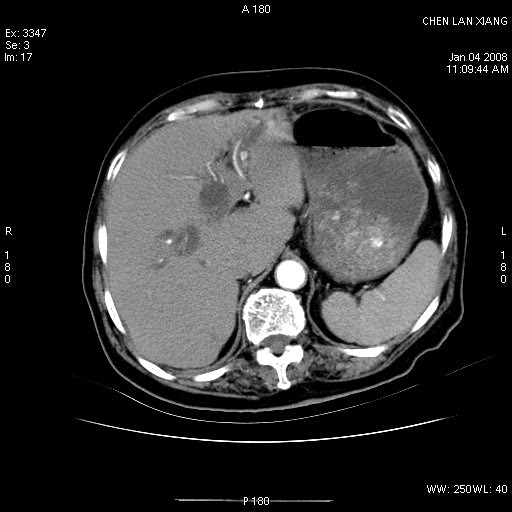

女,76岁,腹痛3-4天,b超示:肝内实性肿物,胆囊强回声,胆总管扩张.

考虑:1、胆总管下端结石伴梗阻性肝内外胆管扩张(肝左叶外侧段肝内胆管多发结石、胆管炎);

2、肿囊癌累及肝,不除外 黄色肉芽肿性胆囊炎。

1 胆总管末端结石伴肝内胆管结石,肝内外胆管扩张。2 胆囊扩大,胆囊壁不规则增厚,内见软组织密度影。考虑:慢性胆囊炎,不除外胆囊癌!

标题: 肝右叶病灶

胆囊癌侵犯肝右叶?

1)胆囊癌伴肝脏转移。2)胆总管下端结石、肝内胆管结石伴肝内外胆管扩张。